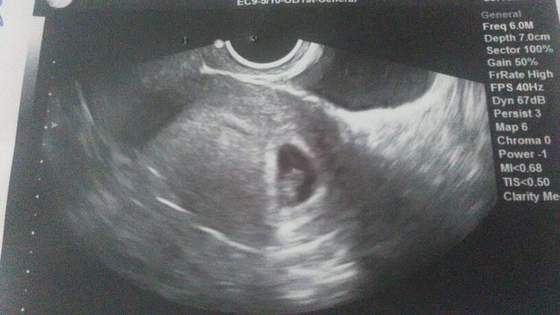

byłam dzisiaj po wpis i przy okazji zrobiłam zdjęcie maluszka z karty. Postaram się dołączyć pierwsze oficjalne zdjęcie naszego robaczka :-)

A to zdjęcie z ostatniej soboty :-)